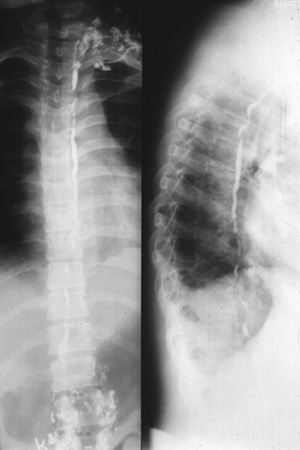

| The thoracic duct drains most of the lymphatic channels in the body into the right subclavian vein. The normal thoracic duct, which lies in the posterior chest just to the left of the vertebral column, is shown here in PA view in the left panel and in oblique view in the right panel with a lymphangiogram, a procedure rarely performed. |